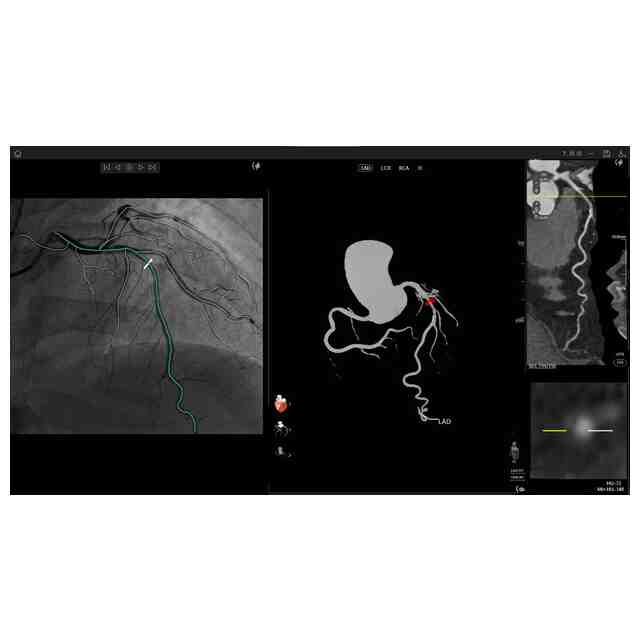

医療データ分析用画像

画像図及び変化後を示す画像図1~3は、例えば、複数の医療用画像を登録した後に表示して分析するために用いられる。使用状態を示す参考図1~6、変化後を示す画像図1の使用状態を示す参考図1~5、変化後を示す画像図2の使用状態を示す参考図、及び、変化後を示す画像図3の使用状態を示す参考図は、医療用画像データを分析するに際し、表示される図を示したものである。変化後を示す画像図1は、画像図における下方において黄色で示されたウインドウの右上隅にある「非表示」ボタンが押されると表示される画像である。変化後を示す画像図2は、変化後を示す画像図1における黄色で示された左端のウインドウがダブルクリックされると表示される画像であり、変化後を示す画像図2における黄色で示されたウインドウがダブルクリックされると画像図に戻る。変化後を示す画像図3は、画像図における黄色で示された中央のウインドウがダブルクリックされると表示される画像である。

図面中、黄色で示された部分以外の部分が部分意匠として意匠登録を受けようとする部分である。